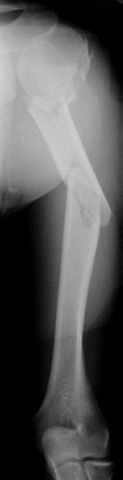

Многооскольчатый перелом плеча

Мужчина 35 лет доставлен к нам через неделю после автотравмы - был в машине. Получил перелом вертлужной впадины (надо оперировать) и открытый многооскольчатый перелом плеча

(рана по преденей поверхности 5 см, ушита неделю назад - сейчас все спокойно), по поводу которого и вопрос - что с таким повреждением делать? Снимок кладу один, поскольку на втором практически та же проекция. Заранее спасибо.

Если я не ошибаюсь, плечо фрагментировано на шесть (!) отломков, и если "про оперативную фиксацию мысли как-то не успокаиваются..." -- металла может потребоваться очень много.

what a terrible fracture !!!!

That is the worst humerus I have seen.

It is very difficult to comment meaningfully without knowing whether or not the proximal humerus is involved and to what extent. There must be some sort of radiograph that shows the proximal humerus better.